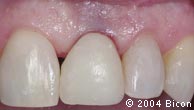

2. | 术前口内的情况可见牙冠变色的中切牙。 |